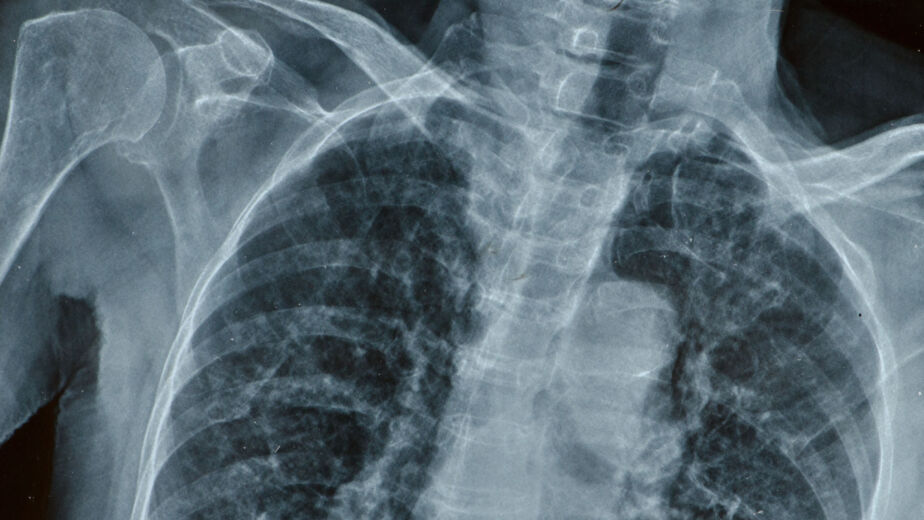

Overnight Paul’s condition deteriorated dramatically. He developed rigid abdomen, rebound tenderness, hypotension and sepsis. When he was readmitted the following morning an erect chest X-ray showed free air under the diaphragm — diagnostic of gastrointestinal perforation. Emergency laparotomy confirmed a large perforation in the posterior duodenal wall caused during the endoscopy. Medical negligence in failing to recognise and investigate post-procedure deterioration allowed peritonitis and sepsis to become established.